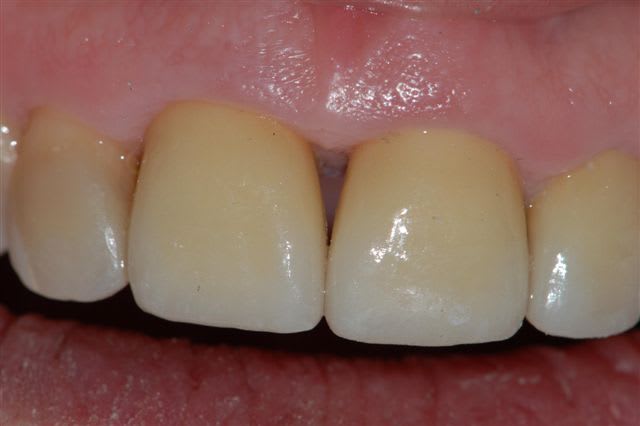

voici un cas traité en dentisterie globale à l'aide du laser en paro et du cerec en occluso, le cas à été terminé en 2010, cette semaine examen microbiologique de routine avec maintenance paro, il n'y a plus de flore pathologique dans la bouche de cette patiente

Emma

Joli cas Emma, juste une remarque, le travail de l'espace inter incisif en jouant sur la convexité des profils d'émergence masquerait le manque immédiat de papille et à terme la papille se reconstruirait plus rapidement.

très belle reconstruction par cfao directe!!!!!